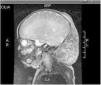

Recién nacida a término (caso 1) con tumoración cervical congénita de coloración violácea, consistencia dura y extensión desde la zona retroauricular izquierda hasta el borde preauricular derecho (fig. 1). La RM confirma el diagnóstico de HEK (fig. 2). Presenta trombocitopenia (25.000/dl) y elevación de D-dímeros (3.000mcg/l), sugestivos de KMS asociado. Inicia tratamiento con metilprednisolona, antiagregación y vincristina, con mejoría transitoria. Posteriormente se produce un descenso de la cifra de plaquetas hasta 5.000/dl en el contexto de una enterocolitis necrotizante. Se decide asociar ciclofosfamida seguido de sirolimus por falta de respuesta, tras lo que se constata disminución paulatina del tamaño tumoral y normalización de parámetros analíticos. Se realizó resección quirúrgica a los 13 meses de vida. A los 22 meses de vida mantiene buena evolución sin recidiva.